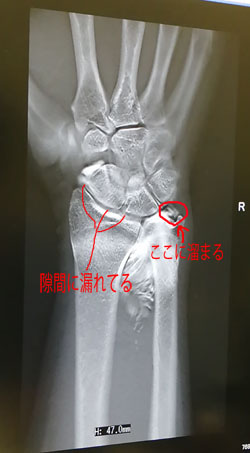

TFCC損傷尺骨突き上げ症候群druj不安定症入院手術尺骨短縮術ギプス手術跡レントゲン入院記録抜釘手術。

尺骨突き上げ症候群S-HANDクリニック 埼玉県さいたま市 手外科。

尺骨突き上げ症候群手の治療専門サイト。

尺骨突き上げ症候群長野整形外科クリニック。